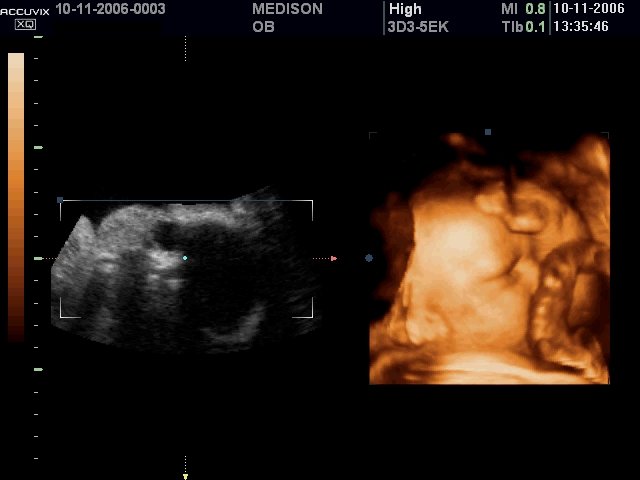

УЗИ сканер Accuvix-XQ (Medison, снят с производства)

Accuvix XQ - ультразвуковой сканер компании Medison экспертного класса (версия XQ) с цветным, двунаправленным энергетическим, тканевым, импульсным и непрерывноволновым допплером, трехмерное УЗИ в реальном времени (3D обычными и 4D объемными датчиками).

- Система Stat 3D - работа с трехмерными датчиками в статическом режиме (3D УЗИ).

- Система Live 3D - трехмерное УЗИ в реальном времени (4D УЗИ).

- Пакет акушерских исследований: биометрия плода, краниологическое исследование плода, исследование длинных костей плода, измерение индекса околоплодных вод (AFI), допплер плода и др. Биометрия плода включает измерения теменно-копчиковой длинны (CRL), размера плодного пузыря (GS), бипариетальный размера головки плода (BPD), затылочно-лобного расстояния (OFD), длины окружности головы плода (НC), передне-заднего размера брюшной полости (APD), поперечного размера брюшной полости (TAD), окружности живота (AC), площади сечения тела (FTA), длины бедра (FL), поперечного (TTD) и передне-заднего (APTD) размеров тела плода. Краниологическое исследование плода включает измерения параметров мозжечка (CEREB), а также внешнего (OOD) и внутреннего (IOD) межглазных расстояний. Исследование длинных костей плода включает измерения длины плечевой кости (Humerus), локтевой кости (Ulna), большеберцовой кости (Tibia), лучевой кости (Rad), ключицы (Clav) и позвоночника (LV).

Объемный датчик 3D 3-5EK/40/69

Трехмерные абдоминальные исследования, акушерство и гинекология.

Объемный датчик 3D 4-8ET/40/84

Трехмерные абдоминальные исследования, акушерство (трехмерное УЗИ плода) и гинекология.